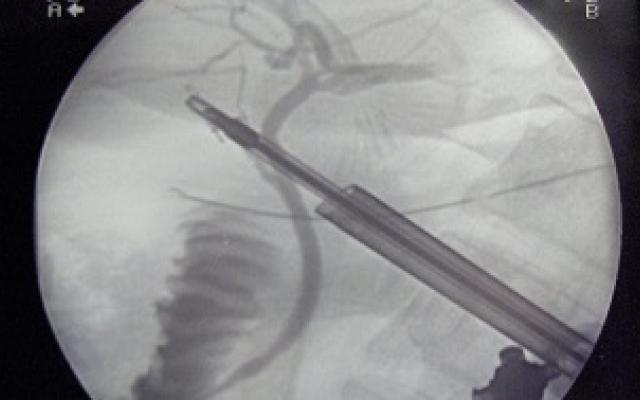

Dit artikel is alleen beschikbaar als PDF.Lees de PDF Artikelinformatie 1 april 1970 Citeer dit artikel als Ned Tijdschr Geneeskd. 1970;114:1522-5 Heb je nog vragen na het lezen van dit artikel? Check onze AI-tool en verbaas je over de antwoorden. ASK NTVG Ook interessant Aankondiging van onderzoek Optimalisatie van indicatiestelling cholecystectomie Nieuws Vroege cholecystectomie nu ook voor ouderen Onderzoek Cholecystectomie à froid en de psyche van de galsteenlijder Meer gerelateerd … Reacties Login om een reactie te plaatsen